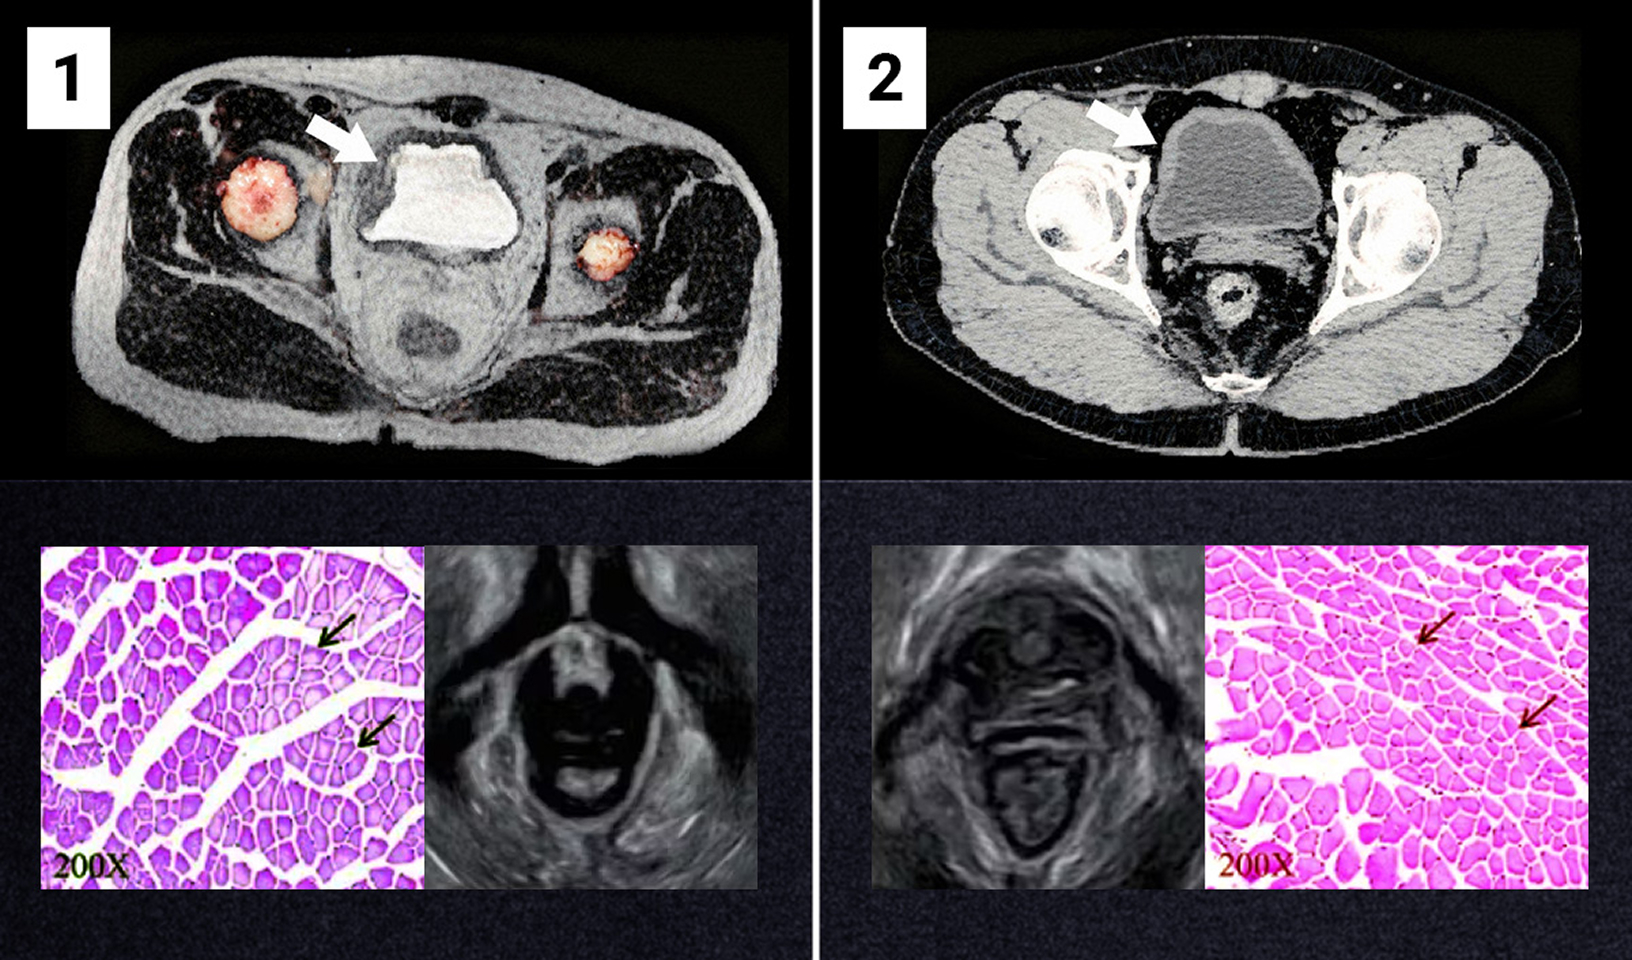

Na obrázku č. 1 je vidět oslabený močový měchýř a ochablé svaly pánevního dna. Snímek pochází od osoby ve věku 47 let, která trpěla inkontinencí moči 12 let.

Obrázek č. 2 ukazuje efekt po 4 týdnech používání bioaktivní metody (na příkladu stejné osoby). Svaly znovu získaly své přirozené napětí. Osoba účastnící se studie přestala mít potíže spojené s inkontinencí moči.

Zdroj: archivní materiály týmu prof. Hansena